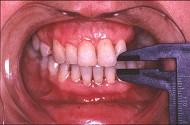

问题 患儿,5岁,外伤后逐渐出现张口困难,咬合关系错乱,髁突动度减弱,外观及X?线检查结果如图。最可能的诊断是()

选项 A.上颌骨骨折 B.下颌骨骨折 C.颧骨骨折 D.颧弓骨折 E.颞下颌关节强直

答案 E